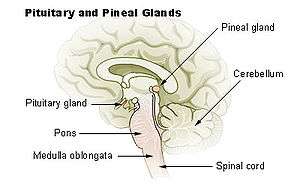

| Pineal gland | |

|---|---|

Diagram of the pineal gland in the human brain. The pineal gland is where the Papillary Tumor is located. | |

Papillary tumors of the pineal region (PTPR) were first described by A. Jouvet et al. in 2003 [1] and were introduced in the World Health Organization (WHO) classification of Central Nervous System (CNS) in 2007.[2] Papillary Tumors of the Pineal Region are located on the pineal gland which is located in the center of the brain. The pineal gland is located on roof of the diencephalon. It is a cone shaped structure dorsal to the midbrain tectum.[3] The tumor appears to be derived from the specialized ependymal cells of the subcommissural organ.[1][4][5] Papillary tumors of the central nervous system and particularly of the pineal region are very rare and so diagnosing them is extremely difficult.[6]